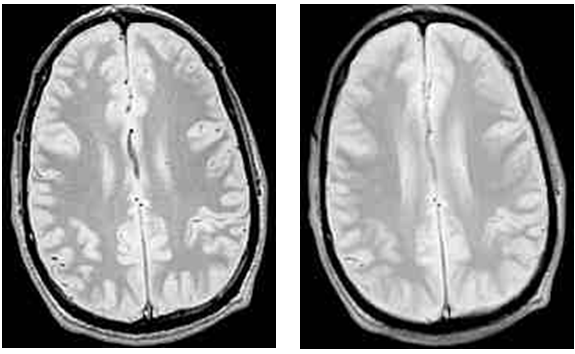

Что касается самих значений, то они обычно представляются в целочисленной шкале от 0 (самый темный пиксель, самая низкая интенсивность сигнала) до N (самый светлый, самая высокая интенсивность). Максимальное значение может составлять от нескольких сотен до десятков тысяч. К сожалению, в МРТ нет единого стандарта, поэтому исследования, проведенные на разных МР-томографах, нельзя сравнивать друг с другом по абсолютным значениям. И даже разные серии одного исследования могут иметь разное распределение значений, т.к. интенсивность сигнала увеличивается с размером вокселя. При иной толщине слайса или размерах пикселей яркость и контраст изображений будет другим.